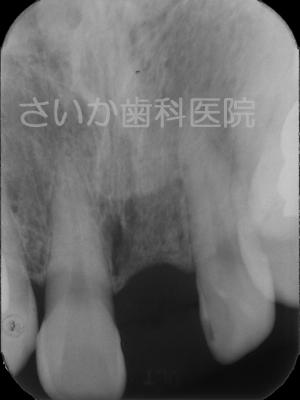

前歯の一本を失ったケースです。この場合もブリッジが選択できますが,健全な歯を削らなくてはいけません。

インプラントで対処しました。上は手術後のレントゲン写真です。